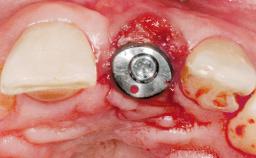

A 30-year-old female patient had lost tooth 21 and was referred to our clinic for consultation and treatment. Due to advanced apical infection, tooth 21 had been extracted two months earlier at another clinic and an acrylic-resin tooth had been bonded to the adjacent teeth. The patient desired implant treatment to avoid any damage to the adjacent natural teeth. While the patient had no history of any systemic disorder, she was a heavy smoker and exhibited medium to advanced periodontitis in the entire jaw. After the initial treatment to achieve a pocket probing depth of less than 4 mm and no bleeding on probing, a decrease in the height of the papillae mesial and distal to the extraction site and overall gingival recession were observed.

Type of Implants One-Piece|Reduced-Diameter

Bone Augmentation Horizontal|Staged

Augmentation Materials Autogenous chips|Membrane

Bone Volume Deficient horizontally, requiring prior grafting